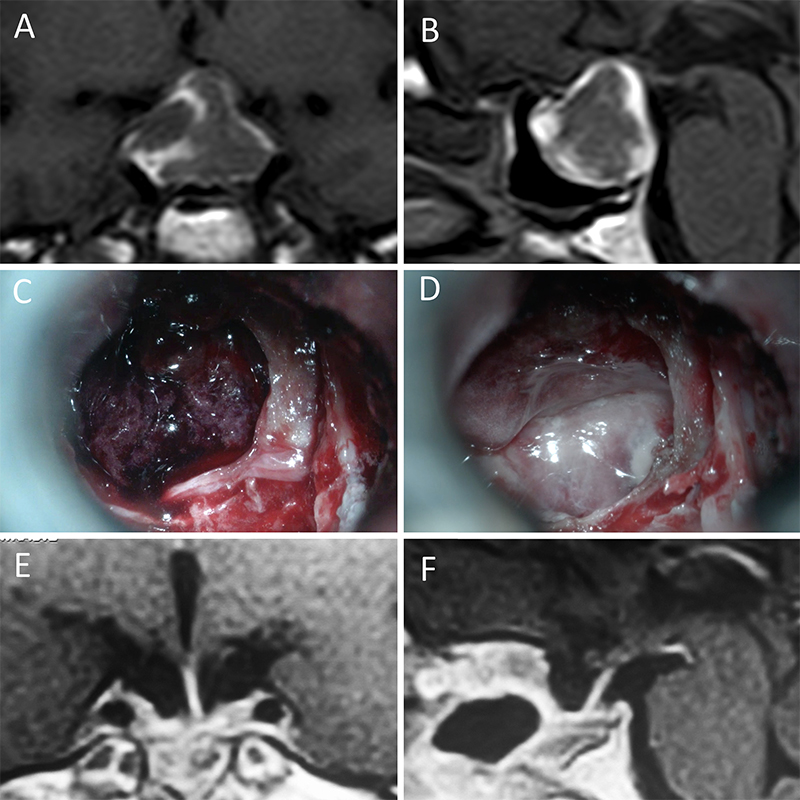

Figura 4: Macroadenoma no funcionante en mujer de 32 años. La paciente presentó en el preoperatorio déficit visual que mejoró tras la cirugía. A-B: RM preoperatoria; C-D: intraoperatorio; E-F: RM postoperatoria.